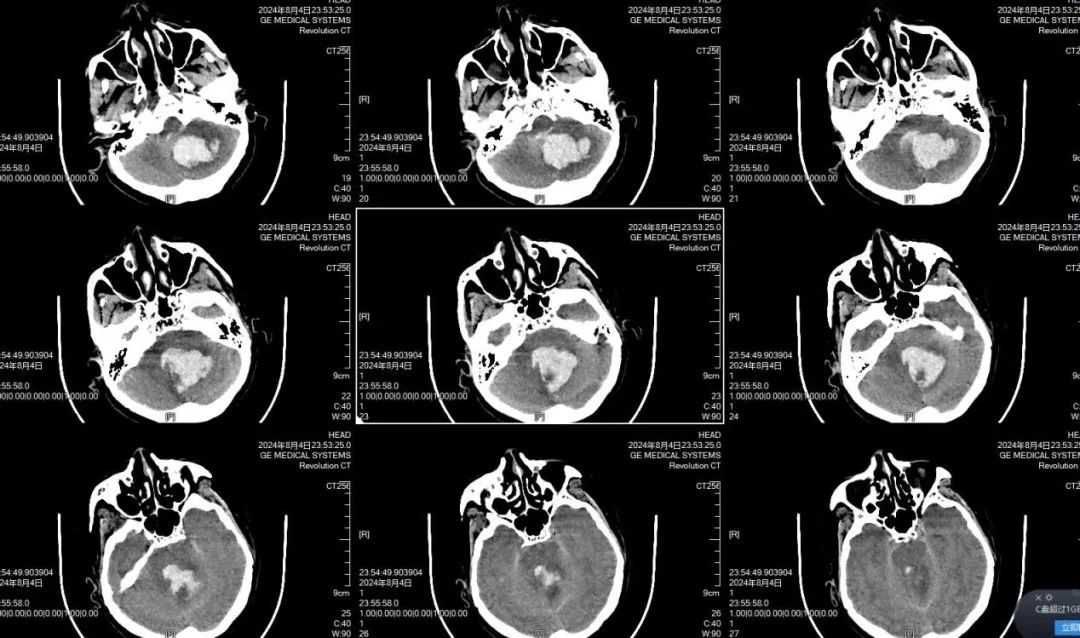

郑维超主任与黄佳荣医生认真听取了家属对病情的详细介绍后,以极其严谨、科学的态度对病情进行分析诊断。他们深知,小脑出血位置特殊,稍有不慎便会危及患者生命。但考虑到患者目前已陷入昏迷状态,为了更加准确地掌握病情变化,他们果断决定对患者再进行一次 CT 检查。11 点 53 分,头部 CT 复查结果显示,小脑出血较之前明显增多,并且伴有急性脑积水。患者病情万分危急,生命危在旦夕,每一秒的拖延都可能带来不可挽回的后果。郑维超主任立即会同神经外科专家组,展开了一场紧张而激烈的病情讨论。凭借着丰富的临床经验和专业知识,迅速制定出一套严谨周密的救治方案。经过深思熟虑,郑维超主任决定立即对重症患者依次进行脑室外引流手术、小脑血肿清除手术以及后颅窝骨瓣减压手术。

凌晨4时,当刘先生看到母亲面容安稳平和的被推出手术室,他的泪水再次夺眶而出,他双手合十,一次又一次地表达着内心深处的感恩之情。患者术后4小时,再次进行头部 CT 复查,结果显示脑室大小已恢复正常,小脑血肿被清理得极为干净。刘先生面向在手术室参与抢救他老母亲生命的全体医务人员,竖起大拇指,微微点头,以无声的方式传达着内心的感激与敬佩之意。